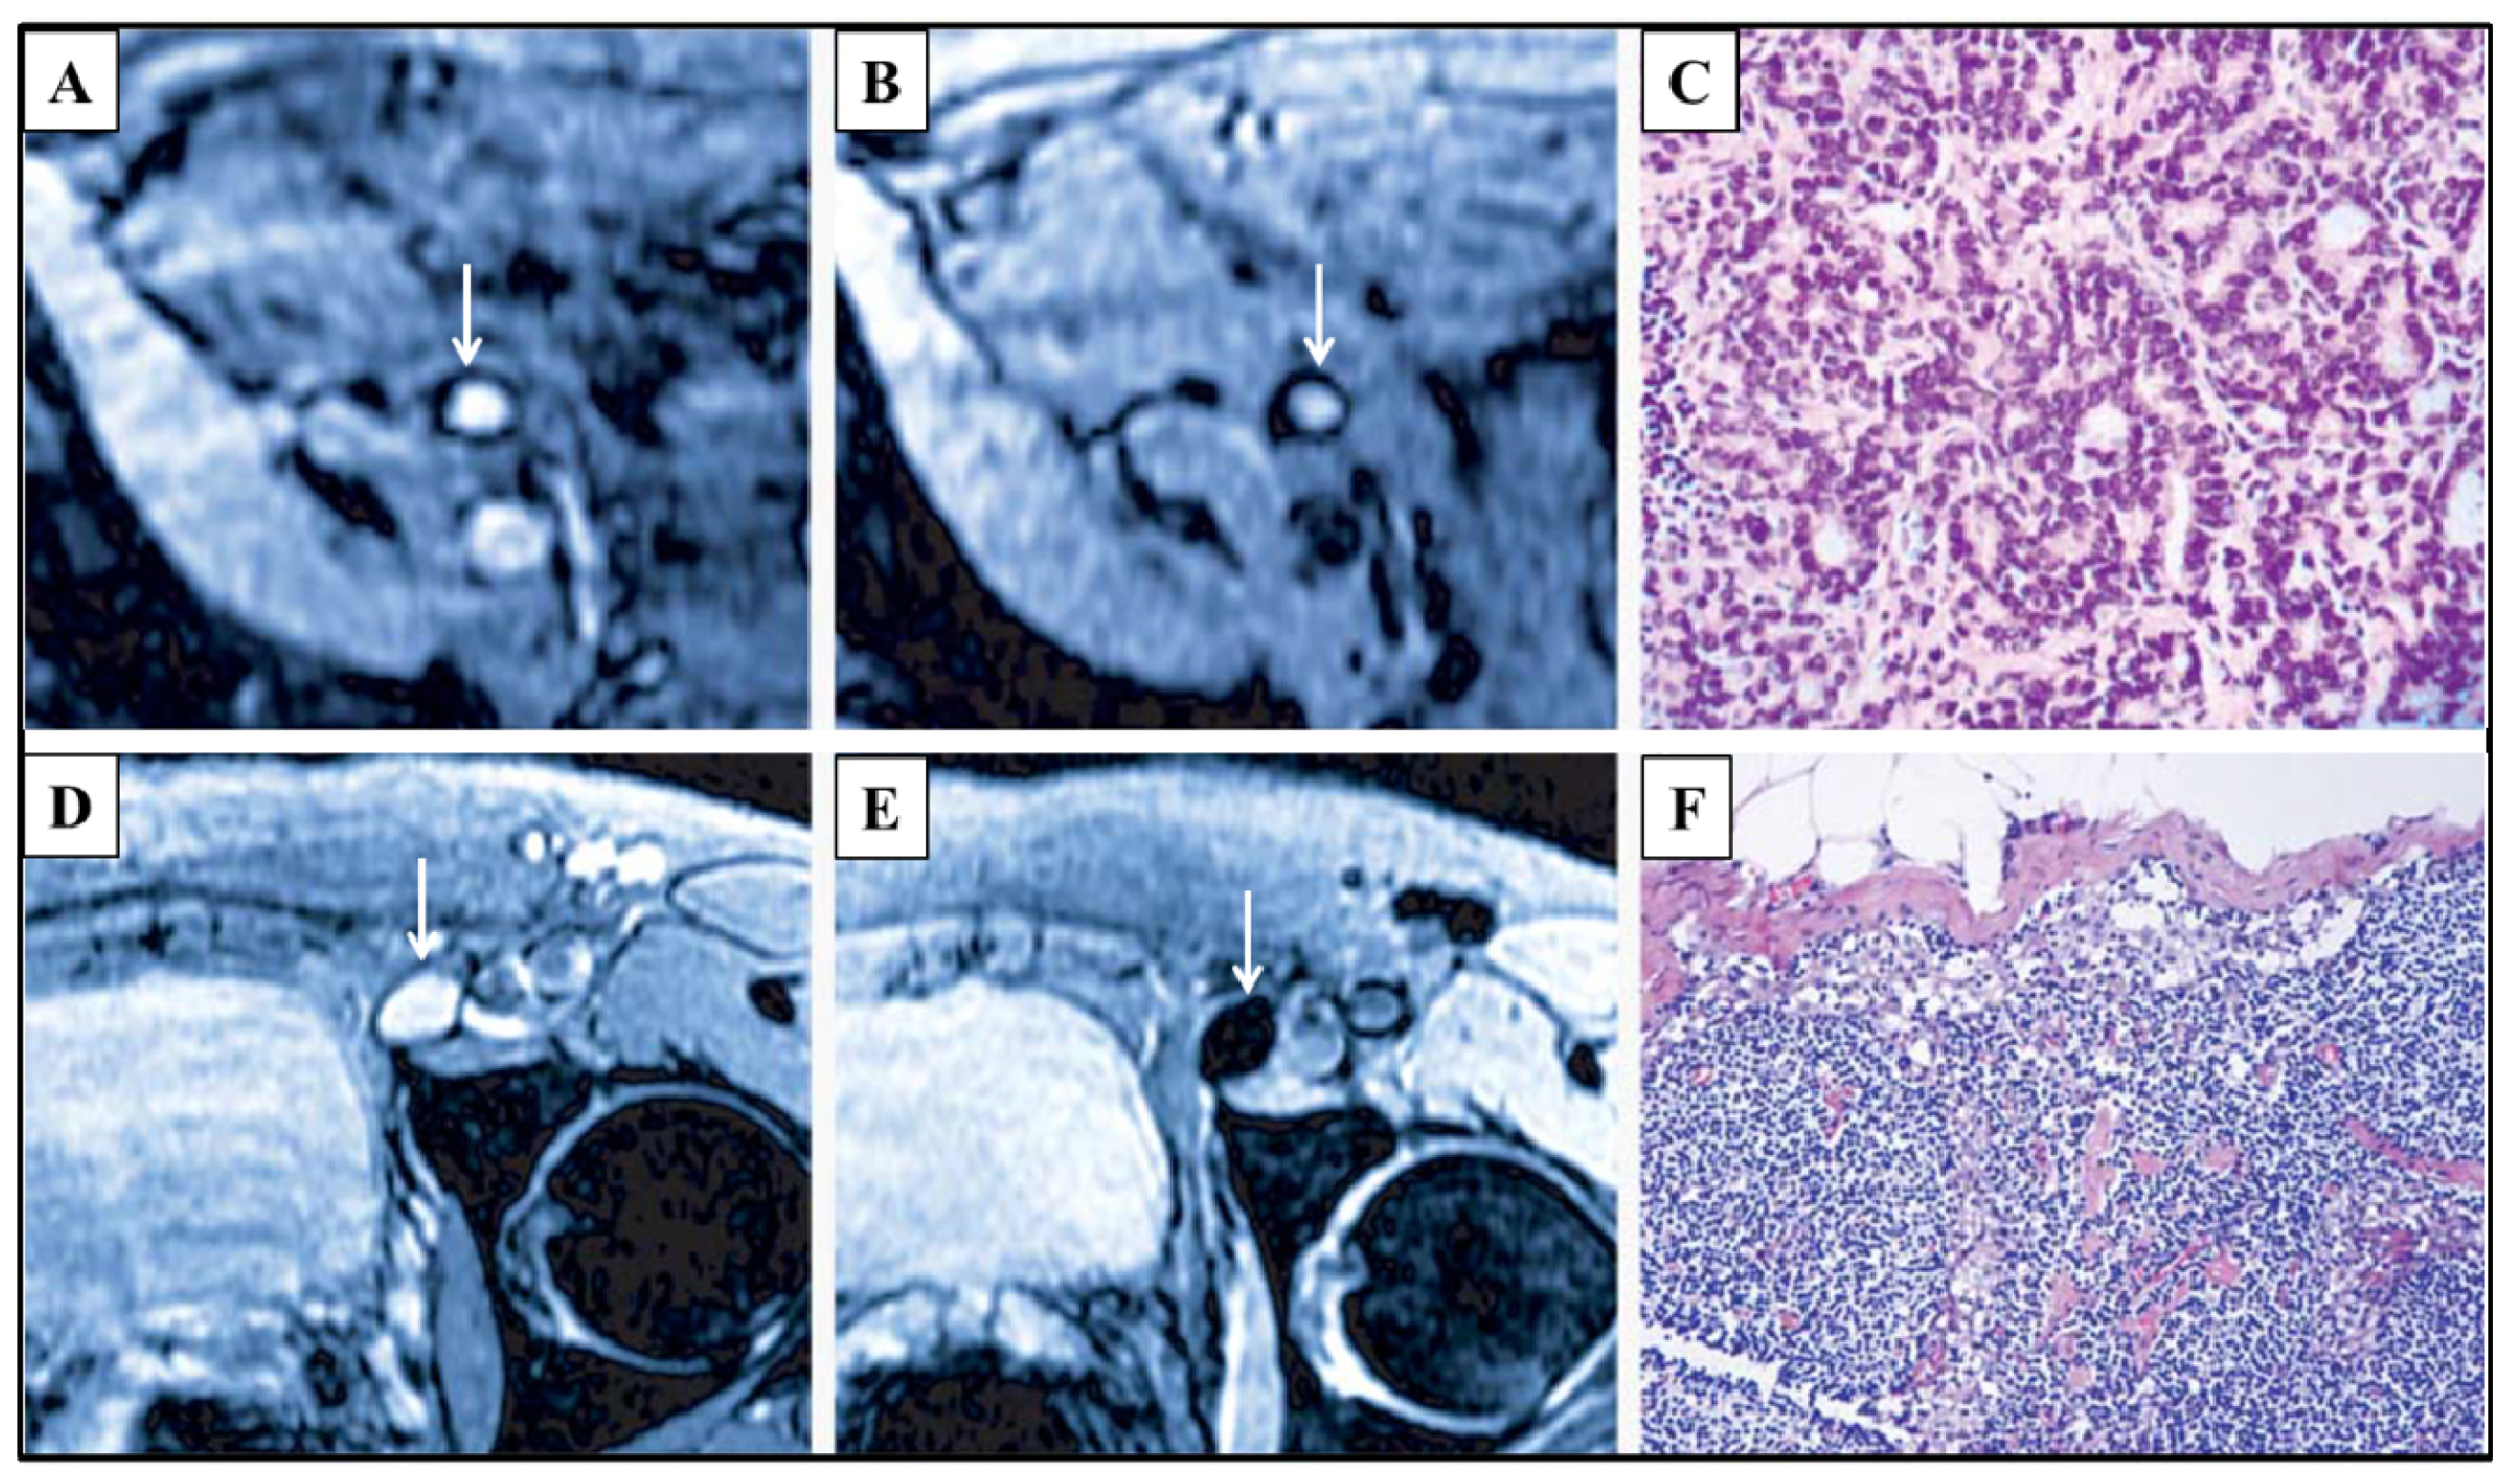

Tumor metastasis turns local cancer into a systematic disease, and lymphatic spread is one of the major mechanisms for tumor metastasis. In most of the malignancies, the situation of lymph node metastasis has major prognostic implications and is a major criterion for determining the necessary adjuvant chemotherapy [105–108]. Sentinel lymph nodes are the first lymphatic relays in the drainage territory of a primary tumor and are considered to be the first metastasis site in lymphatic spread [109–111]. The identification of sentinel lymph node metastasis is important for the determination of the surgery plan and estimation of prognosis. If sentinel lymph node metastasis is negative, the resection of lymph nodes could be reduced, and consequently, patients could benefit from the reduced trauma and possibly extended life expectancy. It has been reported that SPIO nanoparticles can be taken up by macrophages and then transported to lymph nodes [112,113]. As a result, the metastatic lymph nodes lacking macrophages (Figure 6a–c) can be differentiated from the normal lymph nodes that are rich in macrophages (Figure 6d–f) in SPIO-enhanced MRI images [114]. Sinerem, reported as a contrast agent specific to lymph nodes, was applied to prostate cancer and renal cell cancer patients, and lymph node metastases were successfully identified [114–117]. MPI, with the ability to directly quantify Sinerem as a tracer, is a promising alternative to identify lymph node metastasis with high spatial resolution and high sensitivity. If a tracer could be designed to specifically stick to or to be encapsulated into malignant cells, simultaneous imaging of primary tumor and tumor metastases is realizable.

Figure 6.

MRI images were taken from two prostate cancer patients. For one patient, an unenlarged iliac lymph node is completely replaced by tumor and presents high signal intensity in conventional MRI (arrow in Panel A) and Sinerem enhanced MRI (arrow in Panel B); The corresponding histological section (Panel C) (hematoxylin and eosin staining, ×200) verifies lymph node metastasis; For the other patient, a normal lymph node presents high signal intensity in conventional MRI (arrow in Panel D); however, it shows a homogenous signal decrease in Sinerem enhanced MRI (arrow in Panel E), due to the accumulation of Sinerem; Panel F shows the corresponding histological section (hematoxylin and eosin staining, ×200). Reprinted with permission from [114].